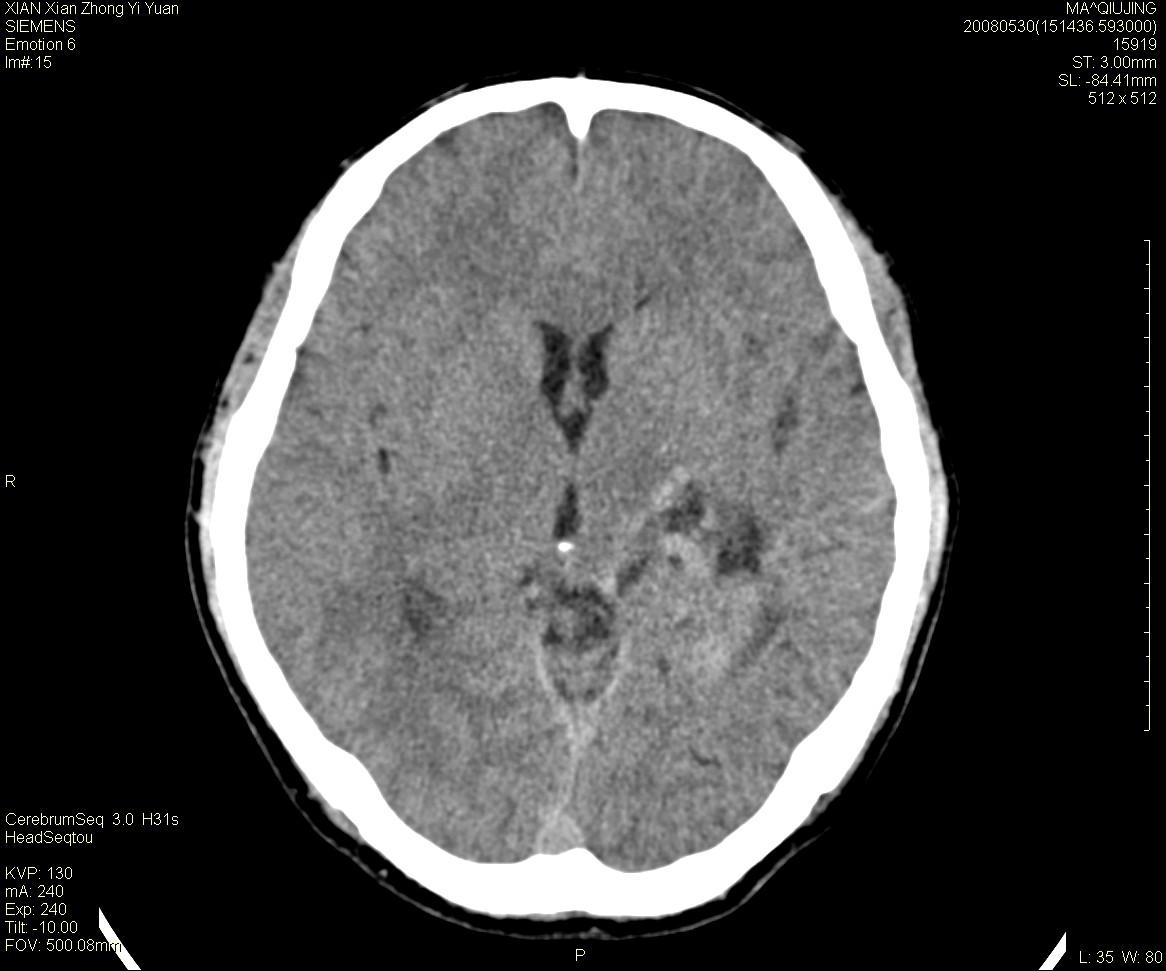

标题: CT13768:少见病例,血管畸形。

患者m47,头晕数年,没给强化,让做dsa去了。

avm

第一感觉:avm,但其中更低密度区不清楚,好像有脂肪密度,胆脂瘤破裂?

avm,低密度区应该是以前出血过的液化灶

血管畸形,支持,如果增强扫描,则可见粗大,迂曲血管团。